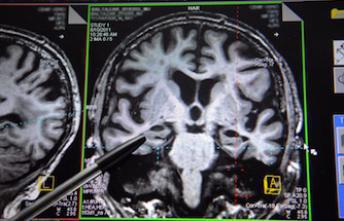

Des chercheurs américains ont indentifié une anomalie dans une zone du cerveau située au niveau de l'hippocampe qui pourrait être en partie responsable de la mort subite du nourisson.

La mort subite du nourrisson (MSN) serait due à une anomalie cérébrale située dans une région du cerveau, à laquelle on associe également l’épilepsie. C’est ce que révèle une nouvelle étude publiée dans le journal Acta Neuropathologia.

40 % de cas de morts subites causés par l’anomalie

Selon des chercheurs américains, la zone en question est le gyrus denté, une structure du cerveau située dans l’hippocampe, la région qui stocke les facultés d’apprentissage et de mémoire. En étudiant les cerveaux de 153 enfants décédés de mort subite du nourrisson, les chercheurs ont constaté une anomalie cérébrale chez 40 % d’entre eux. Alors que le gyrus denté ne possède normalement qu’une seule couche des cellules nerveuses, les chercheurs ont constaté deux couches chez ce pourcentage d’enfants. C’est de cette façon qu’ils sont parvenus à détecter l’anomalie. Selon les chercheurs, cette anomalie provoquerait des lésions et affecterait les fonctions cardiaques et respiratoires, assurées par le gyrus denté. Ce qui expliquerait une partie de ces MSN. Cette anomalie cérébrale n’est cependant pas l’unique cause de mort subite puisqu’elle ne concerne que 40 % des cerveaux des bébés étudiés.